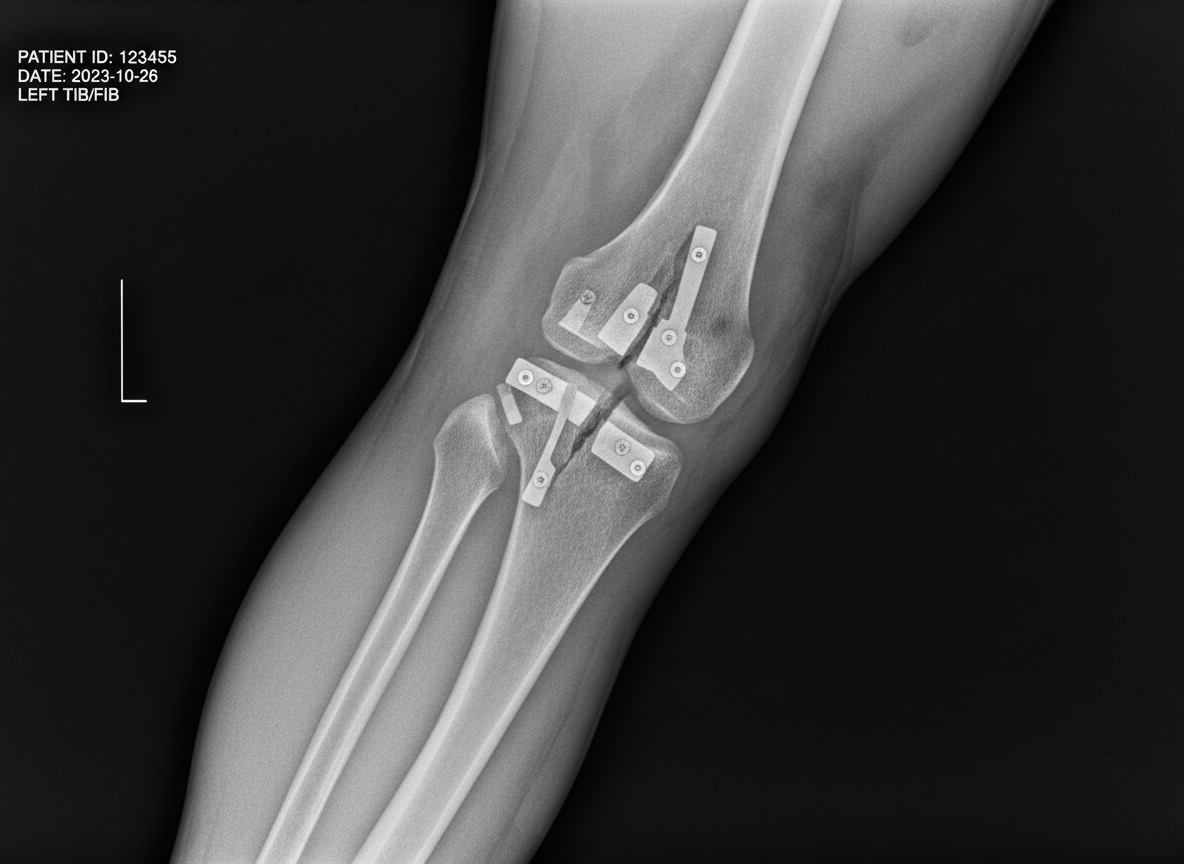

Although uncommon, serious adverse effects are heavily tested and clinically important. Osteonecrosis of the jaw and atypical femur fractures have been associated with long-term bisphosphonate use, making dental health and duration of therapy essential counseling points. Patients should maintain good oral hygiene and ideally complete invasive dental procedures before initiation. Therapy duration should be reassessed after three to five years, as some low-risk patients may benefit from a drug holiday, while higher-risk patients may require continued treatment.